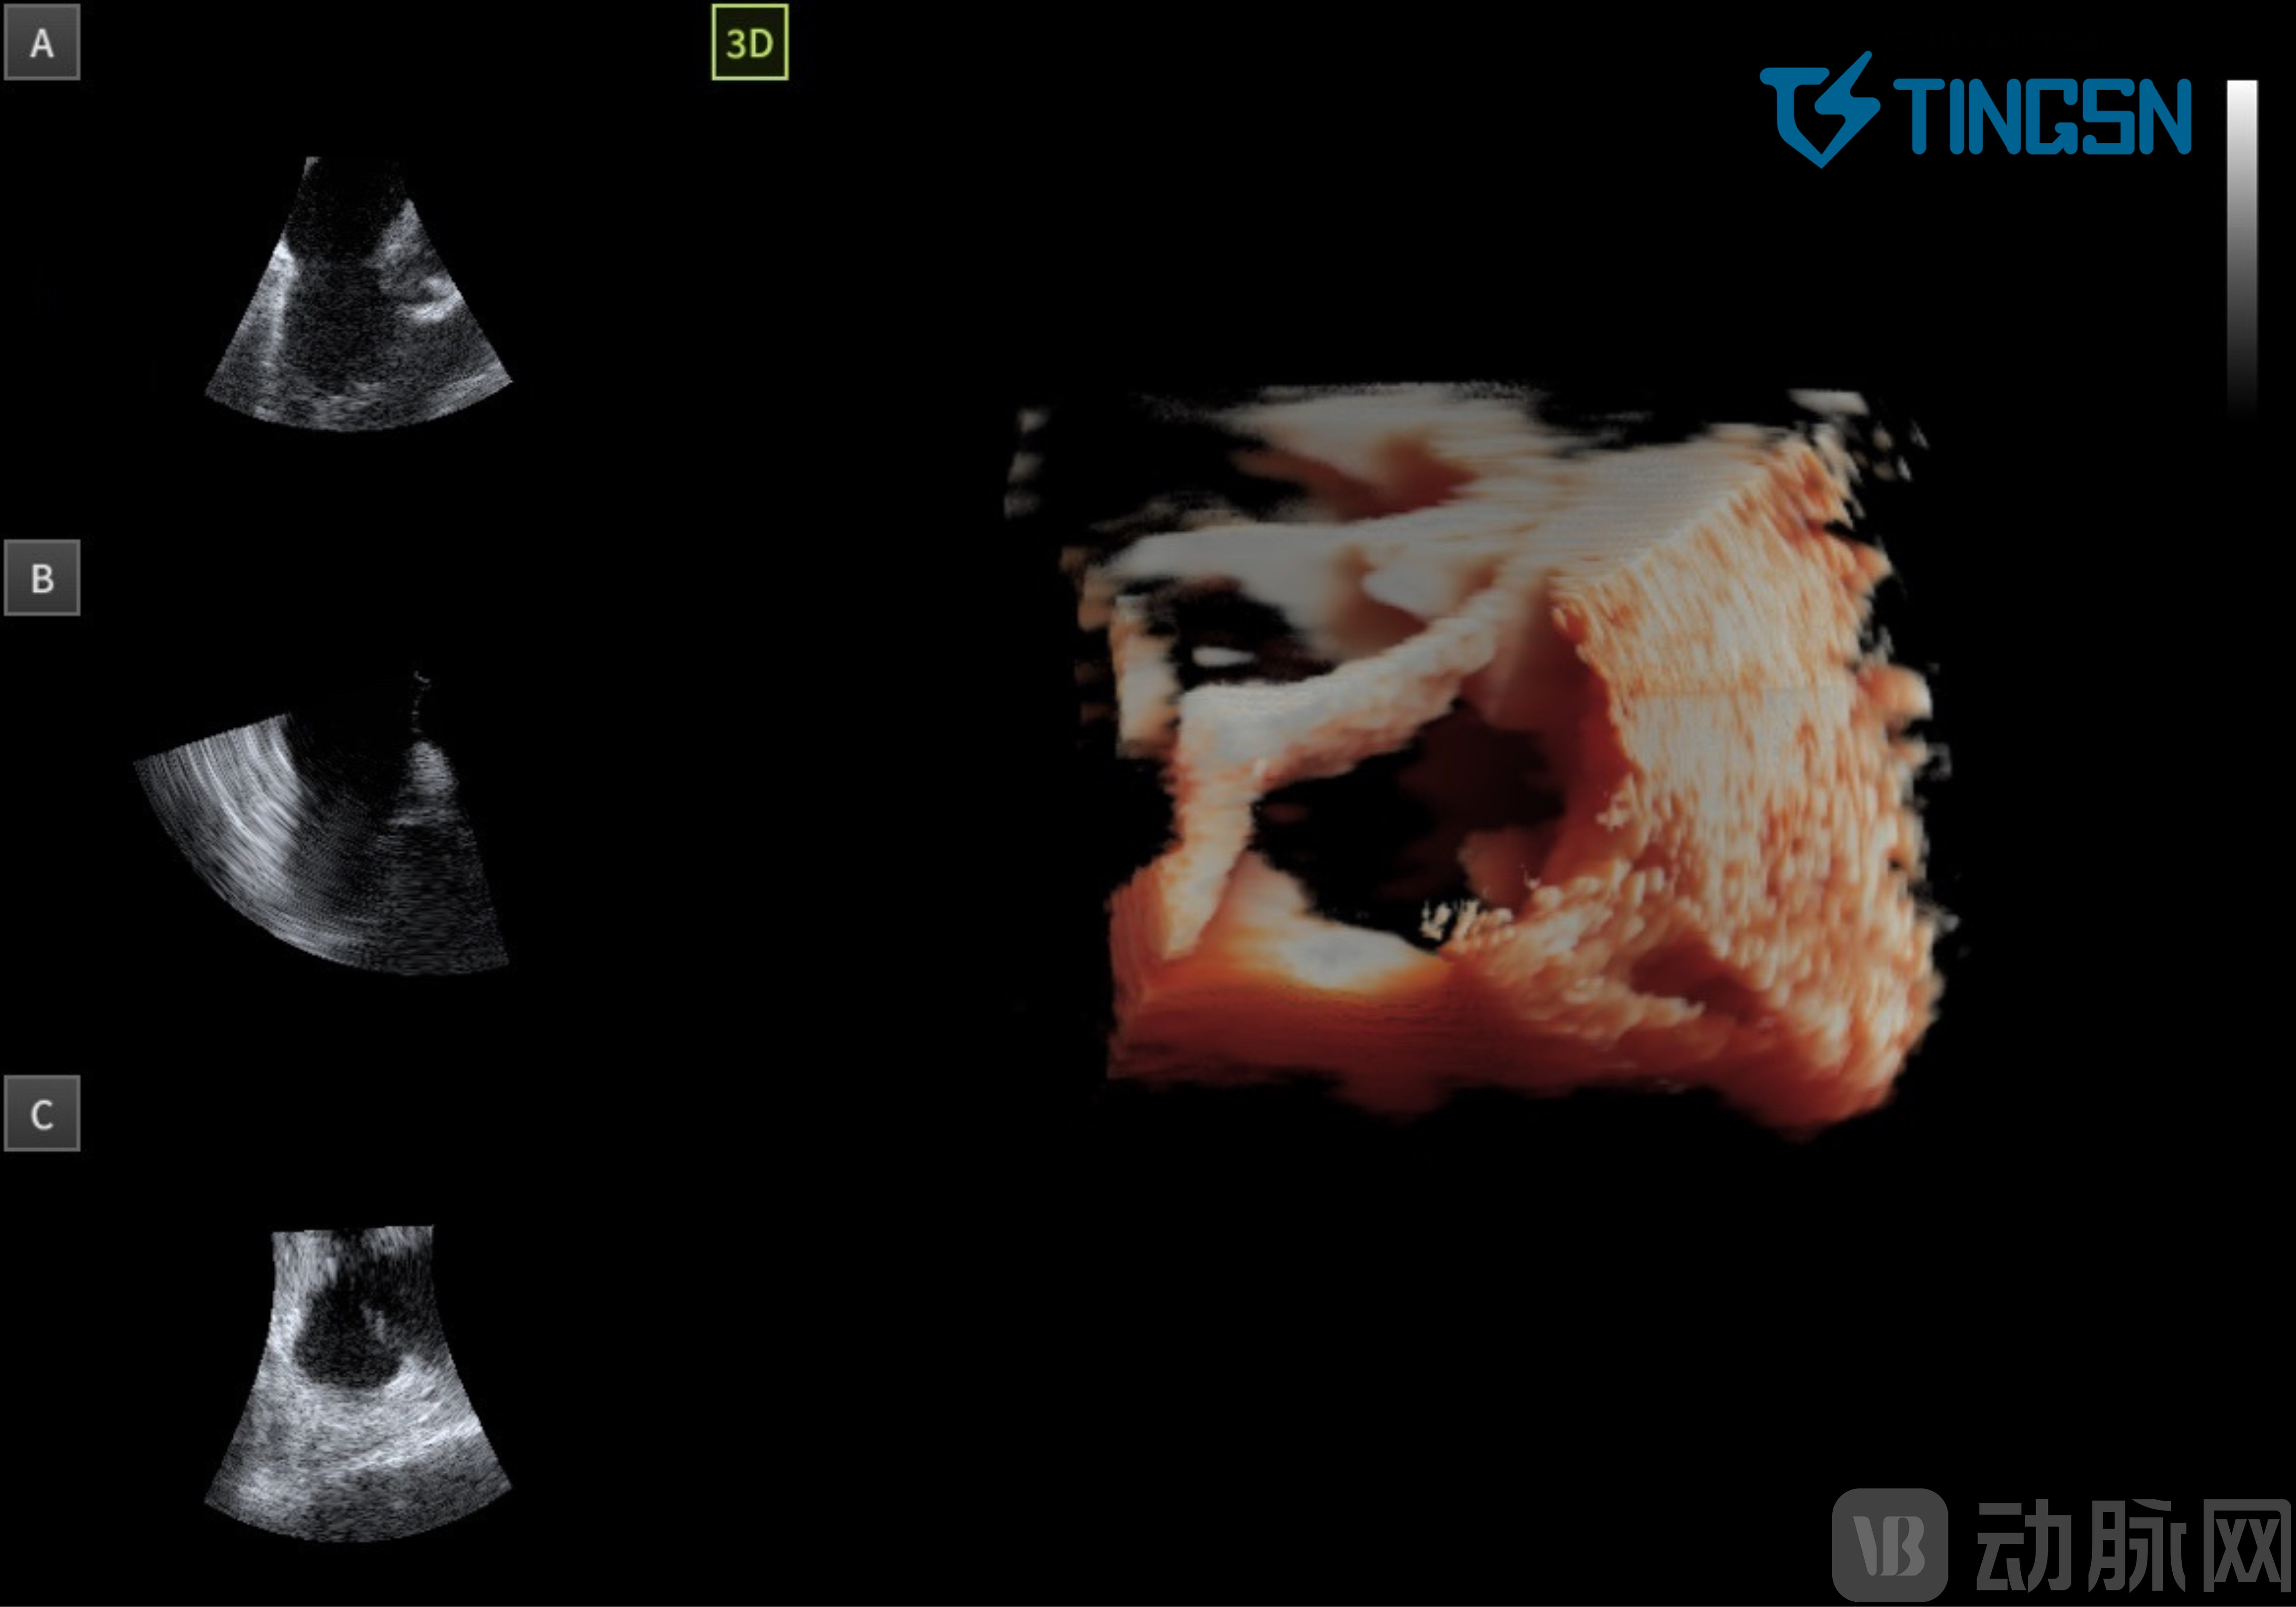

03 左心耳封堵